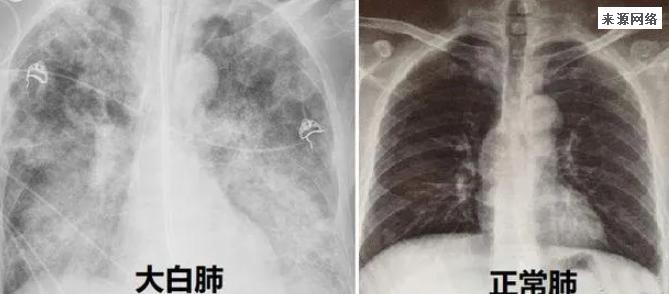

担心老人出现“大白肺”具体怎么观察

提前预警“白肺”有方法